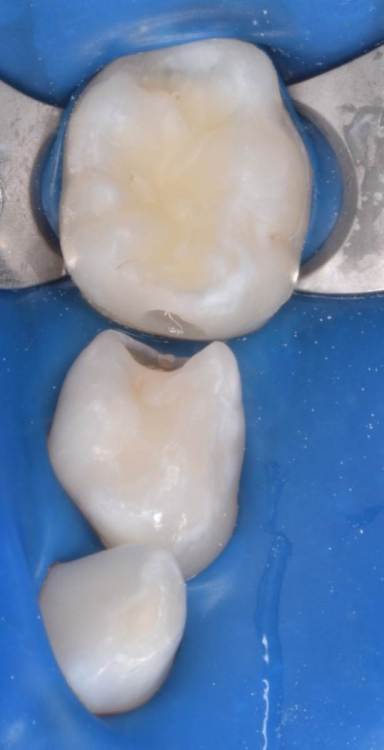

CRAZYDUCK Опубликовано 29 июня, 2022 Автор Поделиться Опубликовано 29 июня, 2022 Герметизация тоже в изоляции . по случаю - герметизация 3.6 лечение кариеса 74 ,75 . 3 1 Ссылка на комментарий